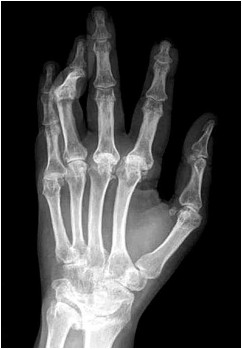

Paciente de 63 anos é avaliada com a radiografia mostrada a seguir:

(Arquivo pessoal; imagem usada com autorização)

Considerando a doença que cursa com a alteração mais relevante detectada no exame de imagem, constitui uma manifestação clinicamente evidente que, mais frequentemente, é encontrada nessa patologia a